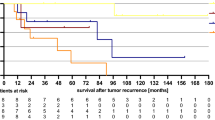

The mean and median follow-up after IMRT and 3D-CRT was 20 months (0.33–76) and 14.7 months, and 47.4 months (1–125) and 46.1 months, respectively. In the IMRT group, rates of CR, PR, and PD were 83.6, 8.2, and 8.2%, respectively, very similar to those among patients treated with 3D-CRT, which were 85.6, 6.7, and 7.7%, respectively (p = 0.608, p = 0.728, p = 0.729). Median overall survival (OS) was not reached for the IMRT group and was 64.2 months for 3D-CRT. There was no statistically significant difference in OS and event-free survival (EFS) (p = 0.971, p = 0.900) (Fig. 1). Local recurrences were found in eight (13.1%) and seven (6.7%) patients in the IMRT and 3D-CRT groups, respectively (p = 0.118). Six (9.8%) and 15 (14.4%) of IMRT and 3D-CRT patients respectively recurred distantly (p = 0.373), the majority of which were to liver, lung, perirectal, and inguinal lymph nodes.